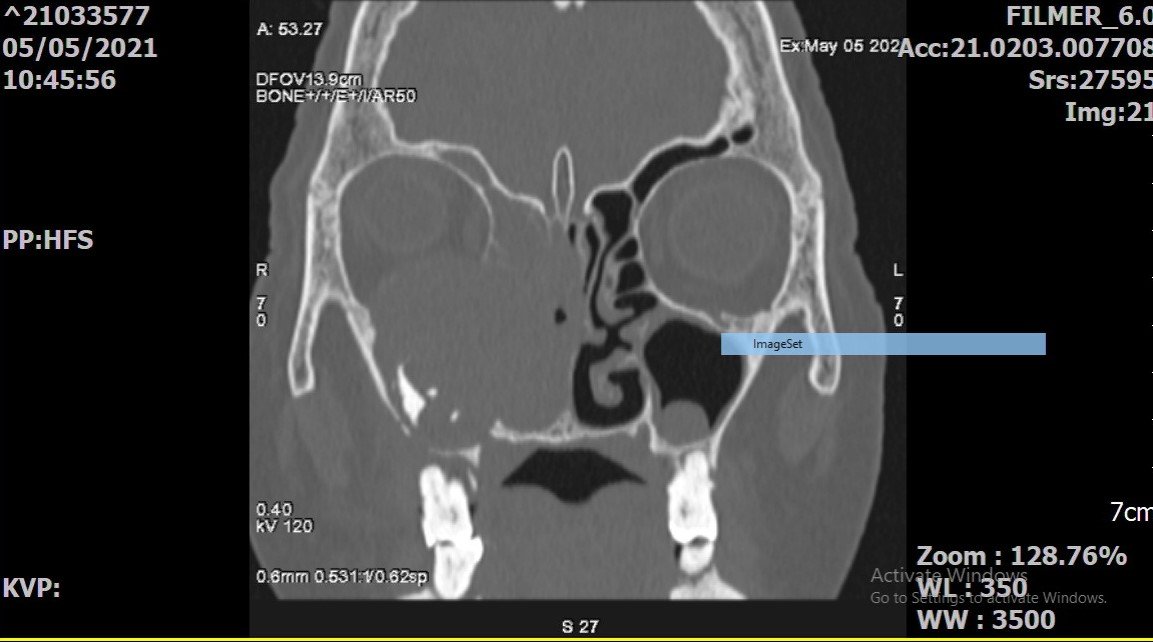

Chỉ còn kém 4 năm là cụ T.T.H tròn 100 tuổi. Khoảng 2 tuần nay, cụ xuất hiện sưng đau mắt bên phải, đã uống thuốc nhưng không đỡ. Gần đây, cụ xuất hiện thêm tình trạng chảy máu mũi bên phải. Cụ được gia đình đưa đến khám tại Bệnh viện đa khoa Quốc tế Hải Phòng. Qua thăm khám và thực hiện chụp CT scanner, bác sĩ Khoa Tai Mũi Họng phát hiện bệnh nhân có khối u từ xoang hàm phải phá vỡ cấu trúc xương của thành xoang hàm xâm lấn vào hốc mũi, phá hủy thành dưới ổ mắt xâm lấn vào trong hốc mắt của bệnh nhân.